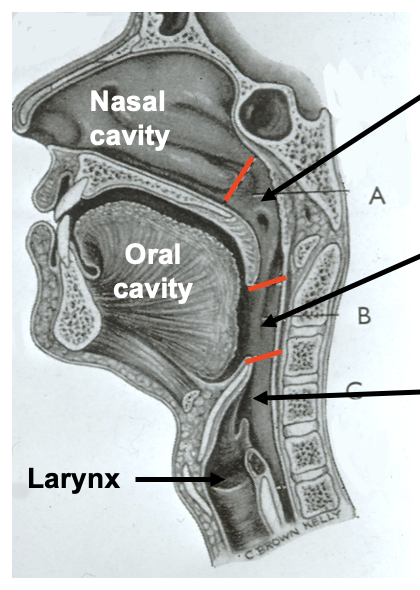

what are the divisions of the pharynx

regions of the pharynx

nasopharynx

oropharynx

laryngopharynx

oropharynx: which vertebrae is it level with posteriorly

body of the second cervical vertebrae

upper part of the third cervical vertebrae

laryngopharynx: borders

laryngopharynx

from the tip of the epiglottis

to the lower border of the cricoid cartilage

laryngopharynx: at which vertebrae is the cricoid cartilage level with

the cricoid cartilage lies at the level of C6

laryngopharynx: at which vertebrae is it level with posteriorly

the laryngopharynx extends posteriorly from the third to the sixth cervical vertebrae